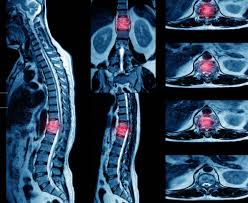

Diagnosis of Tuberculosis Of The Spine

Accurate diagnosis is essential to determine disease severity and prevent complications. Evaluation may include:

• MRI of the spine

• X-ray of spinal segments

• CT scan when required

• Blood tests including ESR and CRP

• TB screening tests and cultures

These assessments help determine infection stage, bone damage, and whether nerves are involved.